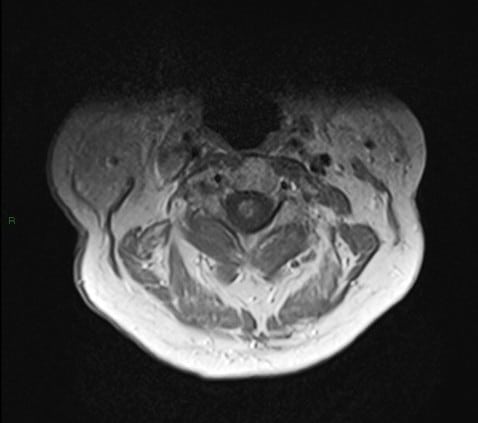

U tủy sống

» Thông tin: Nam giới – 70 tuổi.

» Lâm sàng: Yếu vai phải.

# U sao bào tủy sống (Spinal Astroctyoma) ngang mức C2-C4.